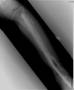

Pre Op

Sustained severe Grade 3 open fracture tibia and fibula with extensive bone loss

Post Op

Initiialy had AO ext fixator followed by muscle flap done. Subsquently had bone transport done in tandem with Orthofix fixator